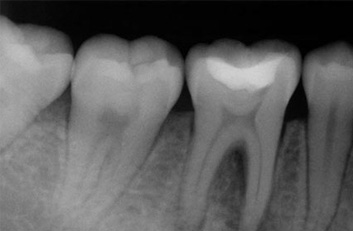

La endodoncia le da más tiempo de vida útil a su pieza dental, en Dental Evolution Cancún le recomendamos evitar la extracción realizándose este procedimiento que garantizamos será sin dolor, gracias a la tecnología de vanguardia con la que contamos, instrumental rotatorio, sistema de ultrasonido, y a nuestra “radiografía digital” la cual juega un papel crucial en el procedimiento de endodoncia, además de que usted estará atendido con la calidez, calidad humana y profesionalismo que caracteriza a nuestro experto equipo de dentistas especializados que le apoyaran en todo momento.